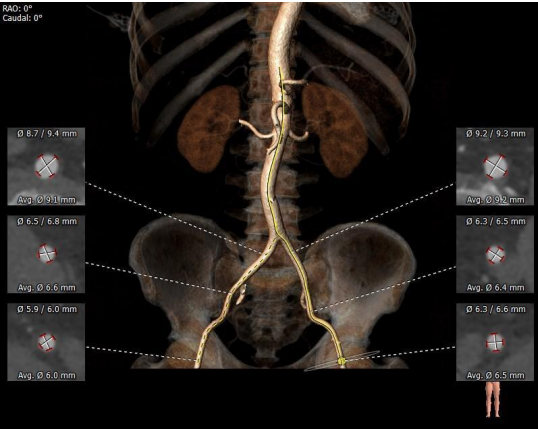

术前CT评估

主动脉根部测量

CT特点:三叶式主动脉瓣,瓣叶轻度钙化,钙化主要位于无窦瓣叶边缘及左右窦交界处,瓣叶显著增厚伴左右窦部分融合;瓦氏窦、窦管交界内径偏小,升主动脉内径可;右冠开口高度可,左冠偏低,瓣叶冗长;非横位心。

瓣上测量

瓣上测量:瓣叶钙化较轻、增厚显著,瓣膜锚定难度稍高;左右窦交界纤维性融合存在一定限制。

弓部及入路评估

入路血管:外周入路走行及血管内径可,整体血管条件良好。